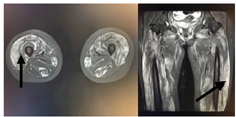

患者,女,20岁,主因"四肢无力9 d,无尿7 d"入院。9 d前无明显诱因出现乏力肌痛,伴随酱油色尿、少尿,当地医院查CK、尿肌红蛋白明显升高,予水化、碱化及透析治疗CK未见明显下降转诊。既往体健,否认用药史。查体:T37.8℃,P120次/min,RR18次/min,Bp147/68 mmHg(1mmHg=0.133Kpa),双侧大腿可见瘀斑,轻度水肿,有压痛,近端肌力4级。双肺呼吸音低,未及啰音,心律齐,腹软,无压痛。辅助检查:血生化ALT1 065 IU/L,AST3 530 IU/L Scr332.7 μmol/L, eGFR16.375 mL/(min·1.73m2),BUN15.27 μmol/L ,CK>8 000 U/L,肌红蛋白>4 140 ng/mL。尿常规:蛋白质+++,红细胞150~180 /HP,WBC100~120/HP。直接抗人球蛋白实验阴性。肌炎抗体阴性。血尿免疫固定电泳未见单克隆免疫球蛋白区带。感染方面筛查:肝炎抗体、CMV/EBV-DNA、呼吸道九种病毒、布氏杆菌、莱姆病、流行性出血热抗体、军团菌皆阴性;高通量病原体检测未检出原核微生物、病毒、真核微生物。重金属筛查阴性。糖化蛋白、甲状腺功能正常。肾脏超声:双肾体积增大且实质回声增强,结构欠清晰。大腿肌肉核磁:双大腿肌肉及双侧下肢肌带肌弥漫水肿,左侧股外侧肌肌筋膜水肿(图1)。入院诊断横纹肌溶解合并急性肾损伤。治疗上,最初间断多次行高通量血液透治疗,血肌酐下降但尿量无明显恢复,且CK水平高居不下。进一步完善的肌肉活检结果(左肱二头肌肌肉)提示:肌纤维坏死、再生,伴随肌束血管周围少量炎细胞浸润,许多肌间毛细血管NSE深染,符合坏死性肌病样病理改变特点(图2)。根据肌肉活检结果考虑免疫介导性坏死性肌病,行激素治疗(甲泼尼龙40 mg/d静点连续10 d后调整为口服泼尼松50 mg口服,静脉激素治疗第3天时曾行甲泼尼龙500 mg静脉冲击1次)及2次血浆置换(每次分别置换3 000 mL)后CK明显下降,尿量也逐渐增多(图3, 图4)。出院时患者口服强的松45 mg/d ,尿量恢复至3 500 mL/d,生化结果:ALT67 U/L,AST26 U/L,Scr99.4 μmol/L,CK78U/L,肌红蛋白23.5 ng/mL,尿肌红蛋白4.6 ng/mL。患者出院1个月后门诊复诊,血肌酐和ck正常,尿量正常,转归良好。

NAM患者肌酶升高以CK为主,一般高于正常值10倍以上,发病初期可达数万。可同时伴有ALT、AST、LDH升高,一些NAM患者血清中肌炎抗体如抗SRP抗体、抗HMGCR抗体、肌炎特异性抗体(myositis specific autoantibody,MSA)可阳性表达。在MRI上,MNM可表现为STIR序列高信号,这提示组织水肿,臀大肌和股四头肌后方肌群受累易见。肌肉病理上,HE染色中,NAM的显著特点是大量肌纤维坏死,可见再生肌纤维。免疫组织化学染色可见肌纤维膜MAC和MHC-I阳性。本例患者为年轻女性,急性起病,双下肢近端肌痛、力弱,CK升高10倍以上,伴随肝酶升高,肌炎抗体阴性,肌肉核磁显示肌肉水肿,肌肉病理提示免疫介导的坏死性肌病,符合上述NAM诊断标准。糖皮质激素是治疗NAM的一线药物,对于病情严重或者初始治疗不佳患者,可给予静注激素。激素效果不佳可应用免疫抑制剂或者静脉应用丙种球蛋白。本例患者确诊NAM后,给予激素和丙种球蛋白治疗,血浆置换辅助治疗后CK、肝酶很快明显下降至正常,临床改善,转归良好。临床上,对经充分水化、特别肾脏替代治疗后CK仍高居不下的横纹肌溶解需考虑有炎性肌肉病可能。可区分MNM患者与横纹肌溶解患者的特征包括:症状和表现(包括CK升高)在不进行免疫抑制治疗时持续存在,进一步完善肌肉影像学检查和肌肉活检明确患者的组织病理学变化。尽早明确诊断、给予免疫调节治疗,可免漏诊误诊、减少患者痛苦。